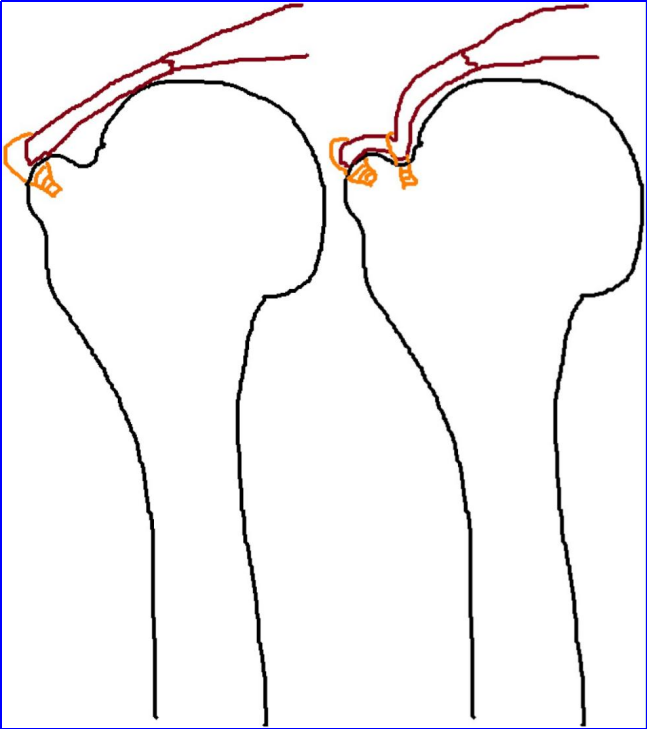

为什么会有单关节器械关节镜下肩袖修复:单排 vs 双排缝合,如何选择?_https://www.jmylbn.com_新闻资讯_第3张

图 2:肩袖撕裂单排修复与双排修复示意图。图源:文献 1

两者的核心差异不是锚钉数量,而是足印区接触面积与初始固定强度。双排能将足印区接触面积提升 30%-50%,同时显著增加界面接触压力,从生物力学角度为腱-骨愈合创造更优条件。理解这一本质差异,是后续所有决策的出发点。